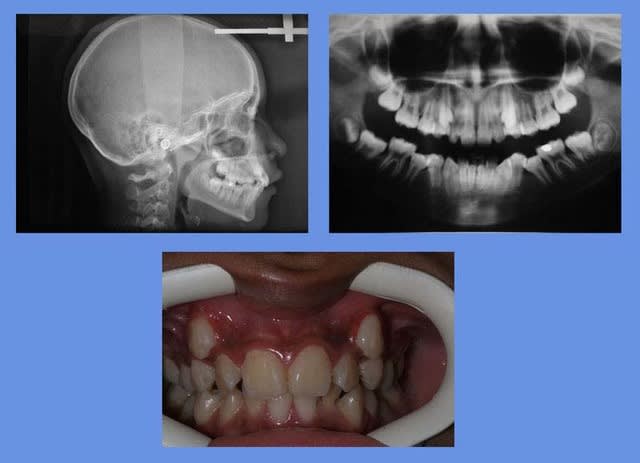

voici un cas d’incisives Inf. qui est une indication d’extraction selon les critères d’il y a 25